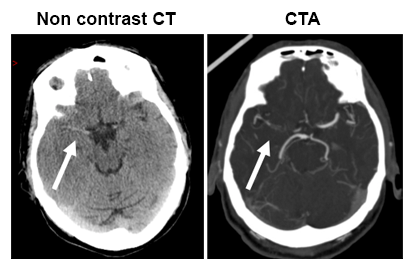

- At 10.05 CT/CTA – shows minor ischaemic changes in right hemisphere, a dense R MCA, CTA confirmed proximal MCA occlusion